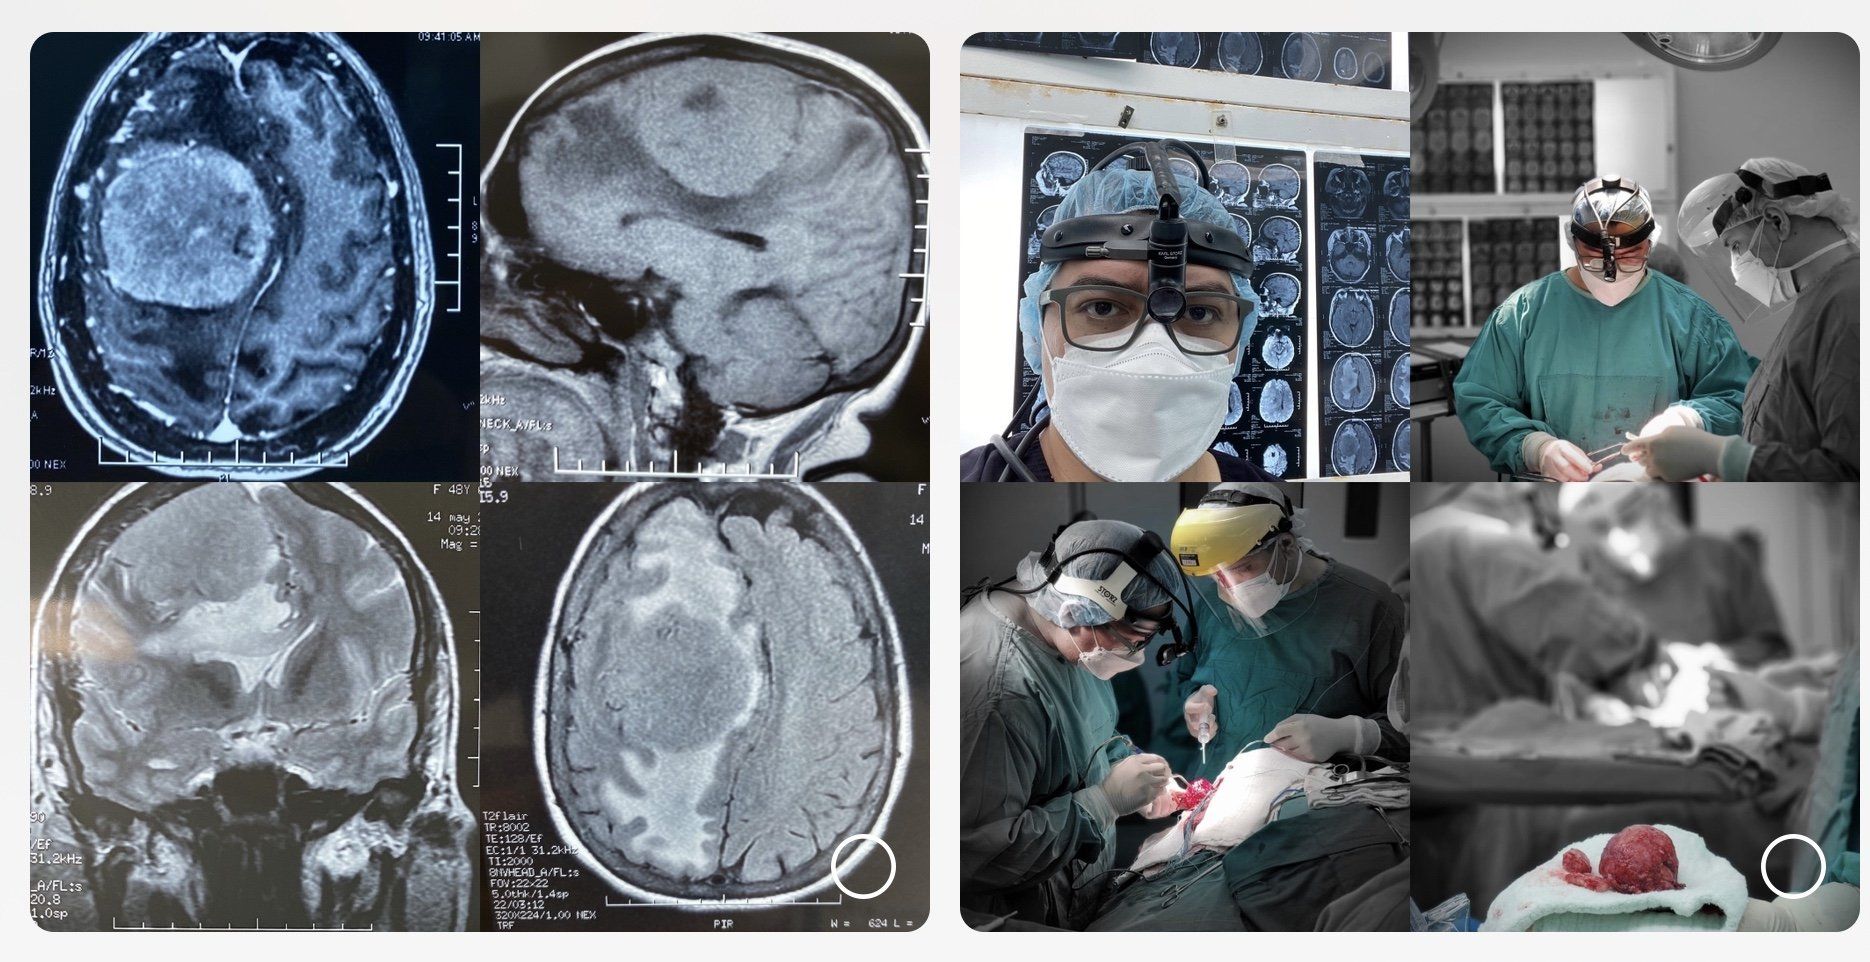

¿Qué enfermedades trata un Neurocirujano?

Las enfermedades neuroquirúrgicas afectan sobre todo al cerebro, cerebelo, médula espinal y nervios periféricos, entre estas patologías se incluyen: enfermedades del disco intervertebral, enfermedades degenerativas causantes de lesiones compresivas de la médula o raíces nerviosas, traumatismos craneales y de columna, tumores cerebrales y medulares, alteraciones de la circulación del líquido cefalorraquídeo (hidrocefalia).